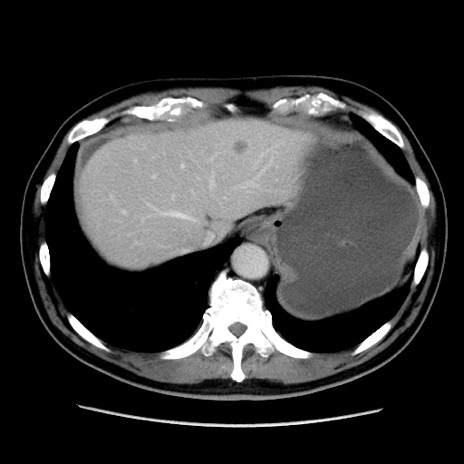

症例16(横断像)

【現病歴】 約1ヶ月前より間欠的に腹痛と嘔吐あり、当院消化器内科を受診したところCTで多発する肝臓のLDAを指摘され、精査中であった。以降は消化器症状は安定していたが、2日前より嘔気と腹痛があり、同日より排便・排ガスが消失した。改善認めず、 本日、救急外来を受診した。